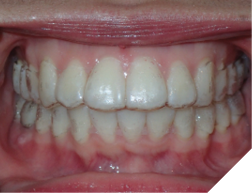

The majority of the orthodontic practices offer a period of “supervised retention” to their patients and communicates the customized retention recommendation with the patient’s general dentists. It is extremely important to work as a team to achieve long term clinical success in maintaining a functional bite and aesthetic smile. The general dentists continue to see their patients on a regular basis and have an opportunity to assess the orthodontic retainers and the bite after the supervised retention period is completed by the orthodontists. With great care, orthodontic retainers would serve for a long time (Fig. 1) without any major issues. However, in some cases, the failure to notice the clinical problems early on results in functional issues that would require a comprehensive orthodontic treatment to correct it (Fig. 2).

Fig. 1A

Fig. 1B

Fig. 1C